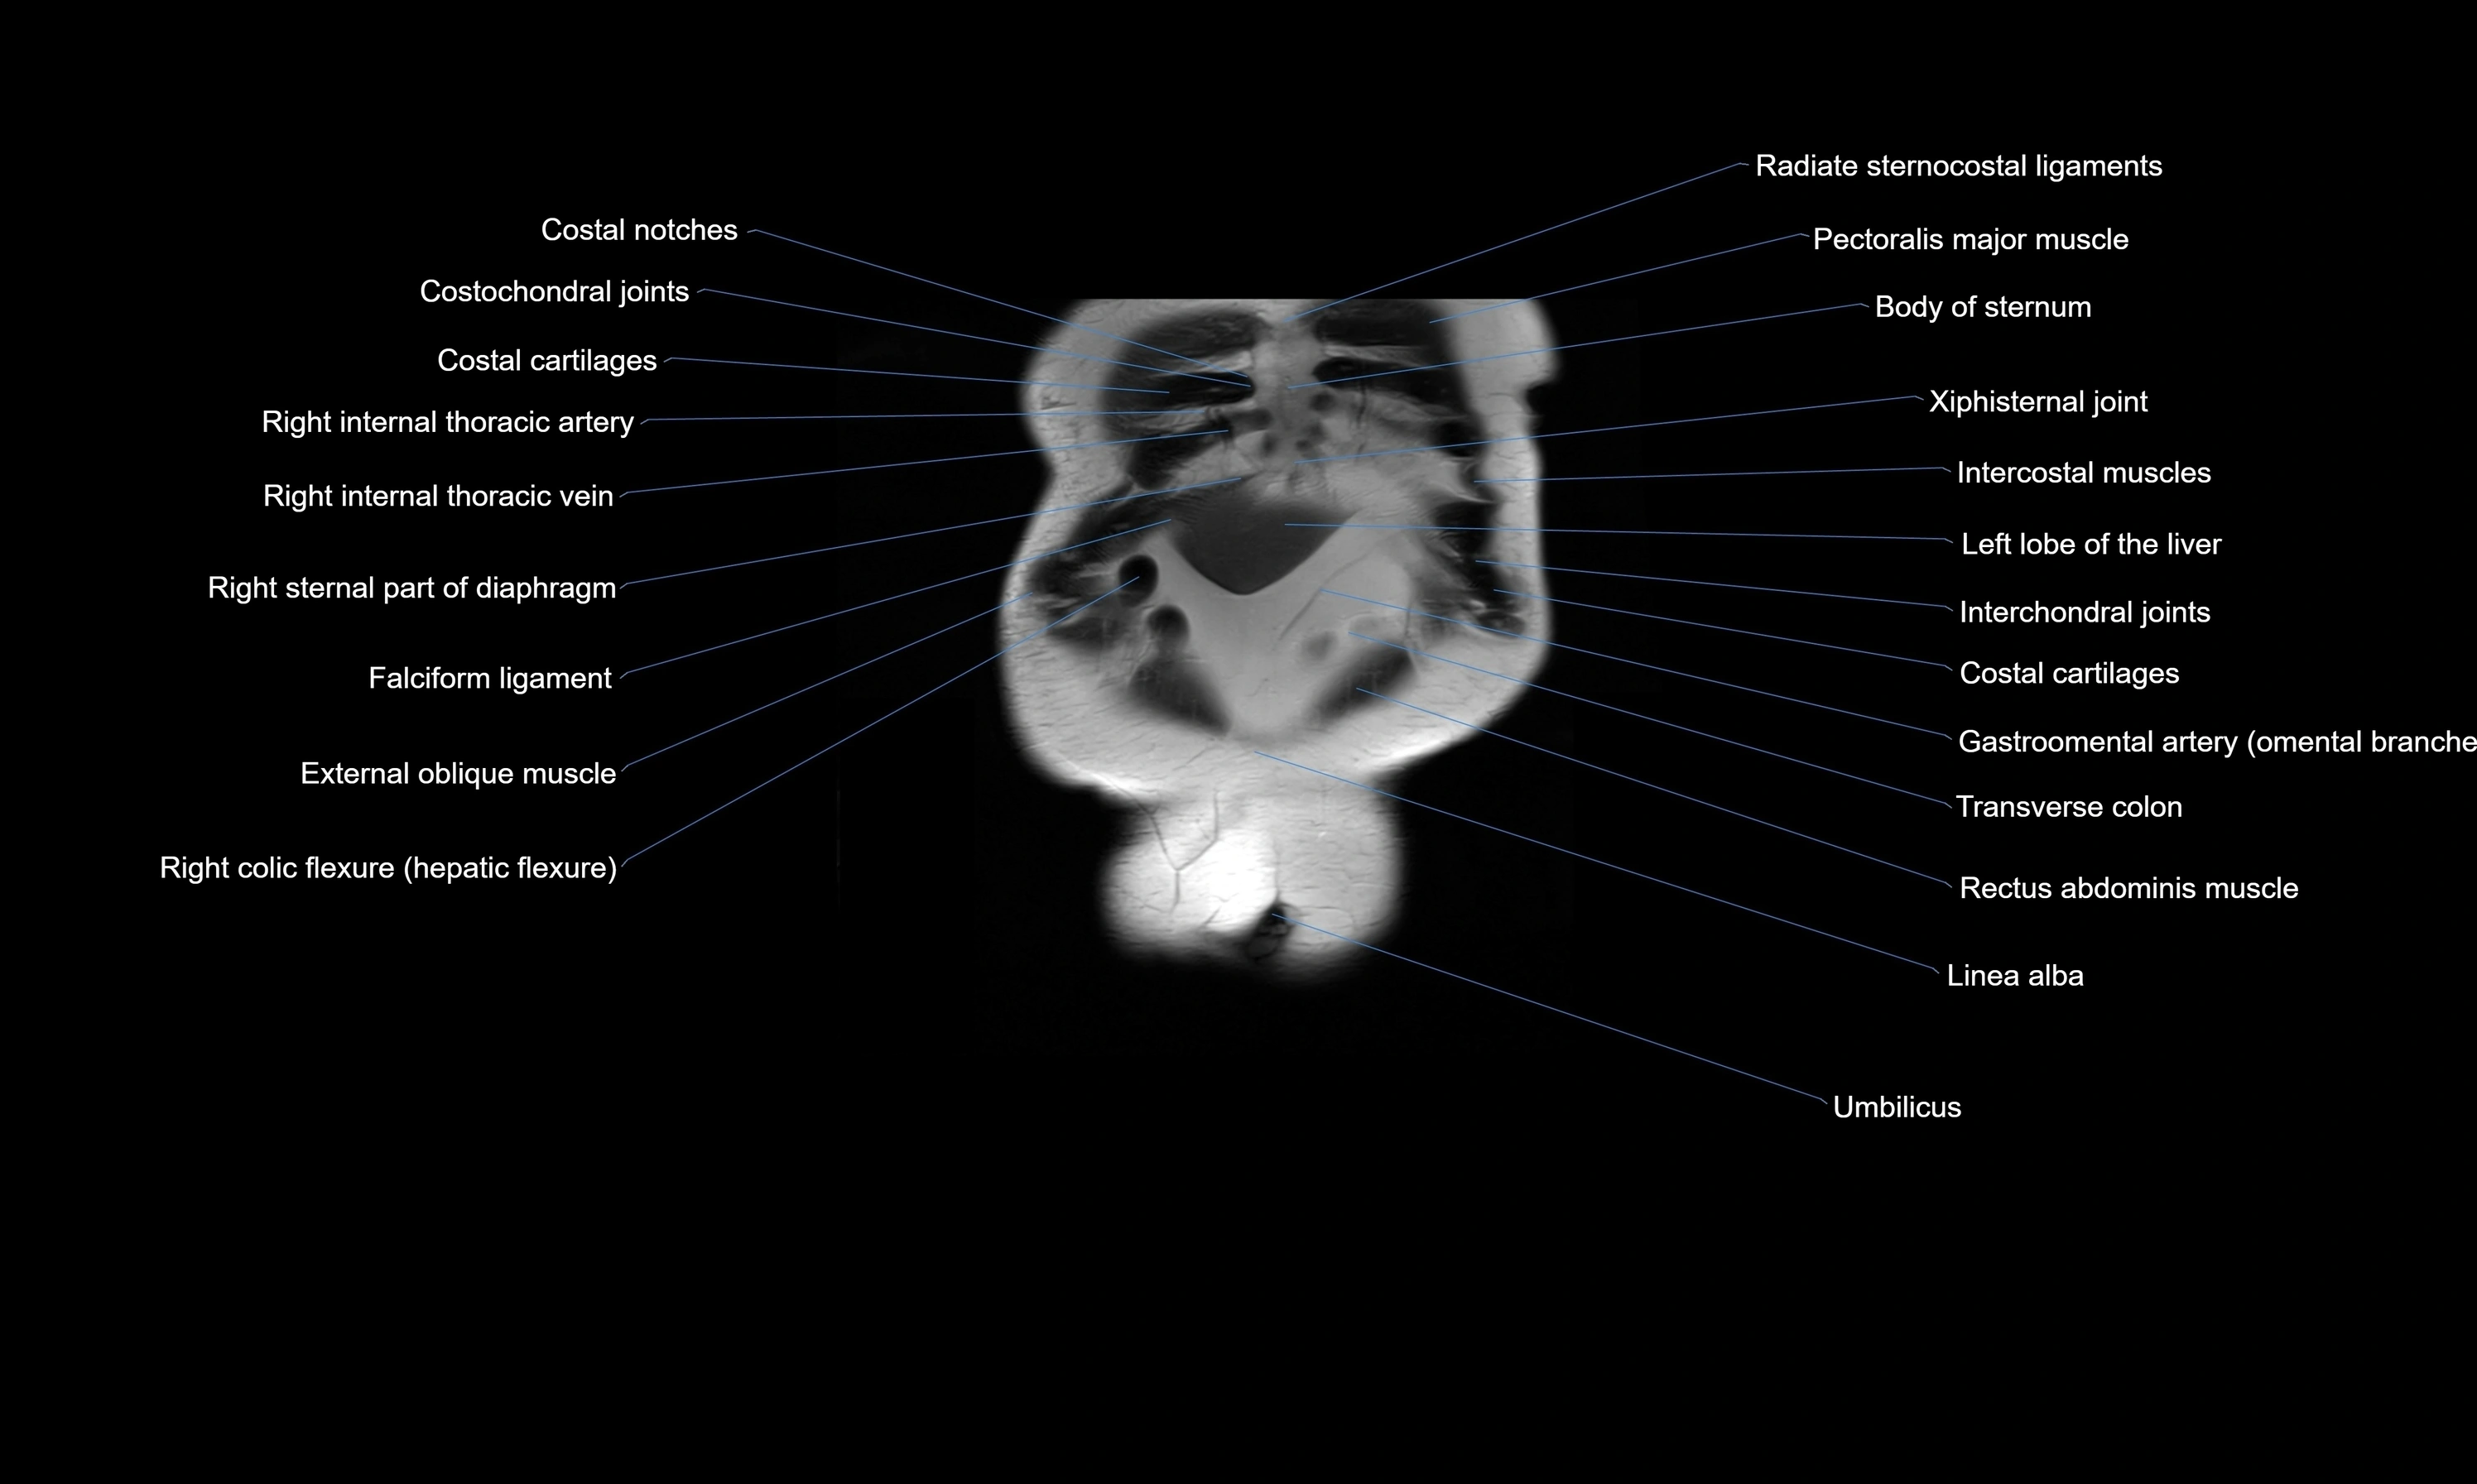

- Costochondral joints

- External oblique muscle

- Intercostal muscles

- Internal thoracic artery

- Internal thoracic veins

- Linea alba

- Rectus abdominis muscle

- Right colic flexure (hepatic flexure)

- Transverse colon